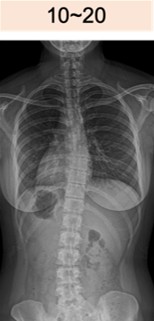

コブ角 10-20度

10~20°